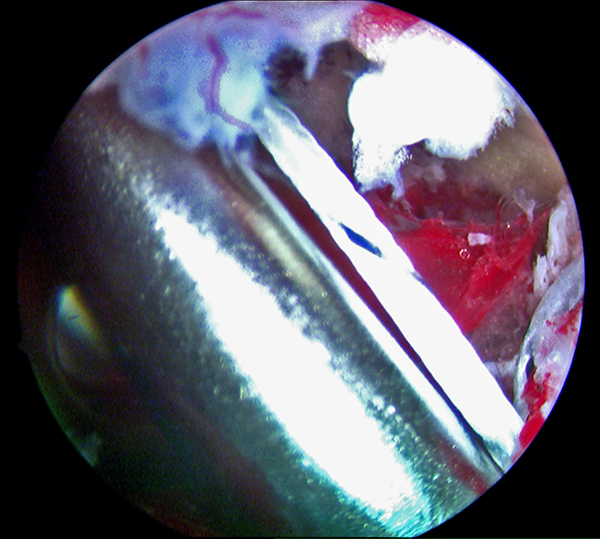

Abbildungen 9-11, Video 3

In maximaler Plantarflexion des Fußes wird die FHL-Sehne durch kräftigen Zug an den Fadenenden nach kranial mobilisiert und soweit wie möglich distal tenotomiert. Die Tenotomie kann mit einer feinen Schere, einem Punch oder mit einem 11er Skalpell über den posteromedialen Arthroskopiezugang durchgeführt werden. Für die Tenotomie sollte eine gute Übersicht vorhanden sein, um eine Verletzung des Gefäß-Nerven-Bündels zu vermeiden. Der Sehnenstumpf wird aus dem posteromedialen Portal ausgeleitet.